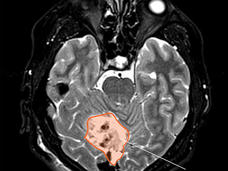

Una prueba permite detectar temprano si quedó cáncer en los niños que se trataron para el meduloblastoma

Una nueva prueba tal vez sirva para identificar a niños con un riesgo alto de que el cáncer vuelva después del tratamiento para el meduloblastoma. La prueba detecta la presencia de cáncer residual en el ADN que se desprende de las células tumorales del meduloblastoma en el líquido cefalorraquídeo.